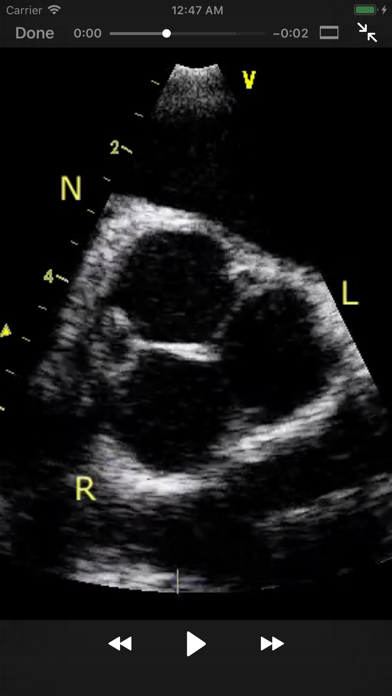

The CARDIO3® ECHOCARDIOGRAPHY project is an app designed as a reference and learning tool for cardiologists, cardiac surgeons, internists, other physicians, and sonographers evaluating echocardiograms for ultrasound diagnosis. The app is edited by Roman Kerekes, MD, Kardio-Vinohradska Cardiology in Prague, Czech Republic. It requires an internet connection and contains 600 annotated videos and growing. Once purchased, the database of videos loading from their server is regularly updated and extended.

2. CARDIO3® ECHOCARDIOGRAPHY project is reference/learning tool for cardiologists, cardiac surgeons, internists, other physicians, and sonographers evaluating echocardiograms for ultrasound diagnosis.

- Main chapters include Basic Principles, Valvular Heart Diseases, Cardiac Masses and Infective Endocarditis, Pulmonary Embolism and the Right Ventricle Function, Cardiomyopathies and Myocarditis, Diseases of the Aorta, Diseases of Pericardium, Congenital Heart Diseases in the Adult, and Cases

- Positive reviews from users, including comments on the image quality, detailed legend, and high-quality echoloops.